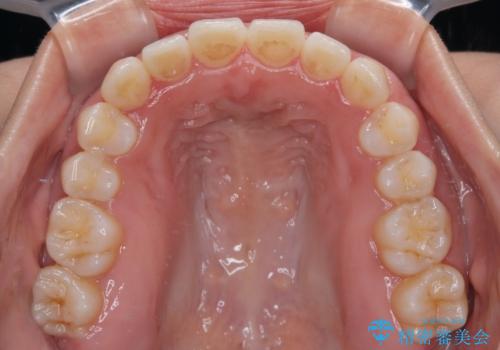

上顎歯列が下顎の歯列に対して狭小であり、一部下顎の奥歯が上顎よりも外側に位置している状態でした。

上顎の急速拡大装置を使用して上顎骨を側方に拡大することで上顎歯列を拡大し、下顎歯列も拡大できるようにすることで、歯列を整えることとしました。